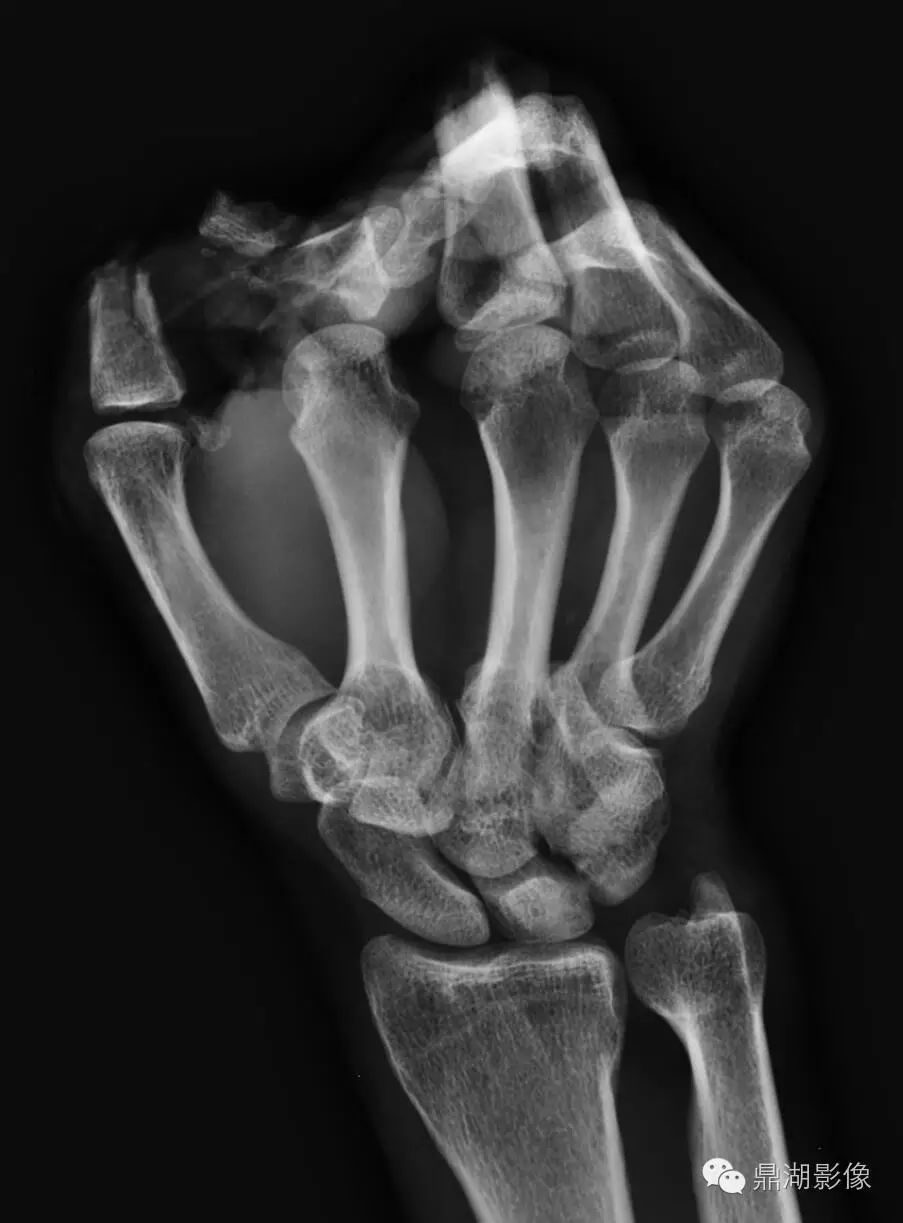

正常人手x光图片,正常右手x光片图片

右手骨骼的x光片

手部x光图片

手腕x光图片

手掌x光图片

手x光片